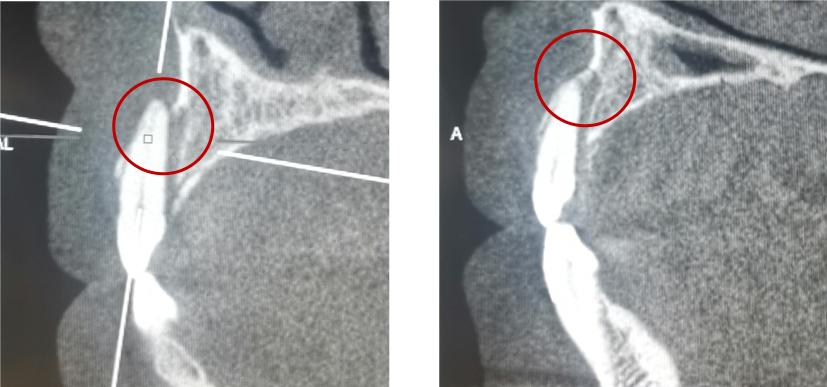

嵌入性脱位

治疗方案: 年轻恒牙:观察自然再萌,若4周内无再萌迹象,则正畸牵引,监测牙髓。成熟恒牙: 嵌入3mm以内 自然再萌,若8周内无变化,外科牵出固定4周,或正畸牵引; 嵌入3-7mm ,外科或正畸牵引; 嵌入7mm以上 ,外科牵引。牙髓坏死,则2周内根管治疗,氢氧化钙根管封药。